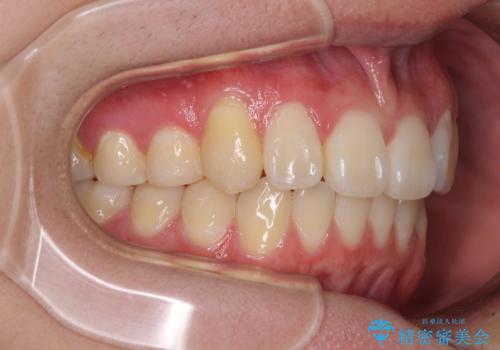

- 八重歯を気にして来院された高校生の患者様です。

ボディーコンタクトの激しい部活動を行っているため、補助装置とインビザラインを用いて、部活動を継続しながら治療を行うこととしました。

八重歯を効率よく改善するため、補助装置を使用して上顎の奥歯を後方に移動させました。

部活動をしながらでしたが、マウスピースをしっかりと装着してくださったので、1年半程度で終了することができました。